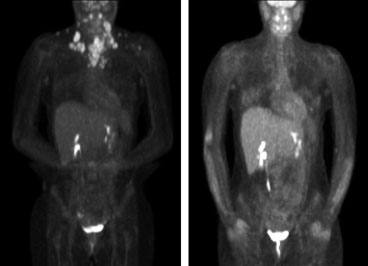

The University of Wisconsin Section of Nuclear Medicine provides image interpretation of a wide range of nuclear medicine procedures including positron emission tomography (PET) examinations.

The section is composed of experts in multiple areas including general nuclear medicine and PET imaging, theranostics, nuclear cardiology, and the imaging and treatment of patients with thyroid cancer. Therapies in patients with various forms of cancer are routinely performed with unsealed sources such as radioactive iodine and labeled antibodies. The section has state-of-the-art imaging equipment including PET/CT and SPECT/CT.